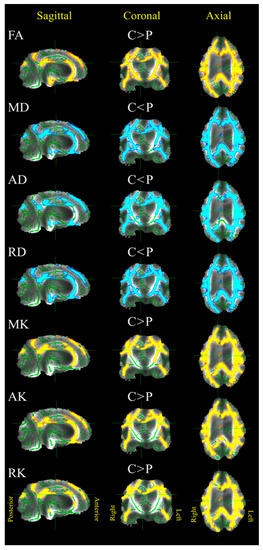

3.1. Patients versus Control Group

| FA | MD (µm2/ms) | AD (µm2/ms) | RD (µm2/ms) | MK | AK | RK | |

|---|---|---|---|---|---|---|---|

| GM | C < P | C < P | C < P | C > P | C > P | C > P | |

| Control | 1.5/0.10 | 1.6/0.11 | 1.4/0.10 | 0.66/0.05 | 0.63/0.03 | 0.66/0.04 | |

| Patient | 2.1/0.45 | 2.3/0.46 | 2.0/0.45 | 0.58/0.25 | 0.52/0.09 | 0.59/0.23 | |

| Cohen’s d | 1.97 | 2.05 | 1.91 | −0.4 | −1.6 | −0.39 | |

| WM | C > P | C < P | C < P | C < P | C > P | C > P | C > P |

| Control | 0.28/0.01 | 1.0/0.08 | 1.3/0.08 | 0.9/0.09 | 0.87/0.05 | 0.76/0.04 | 0.70/0.07 |

| Patient | 0.17/0.03 | 1.6/0.40 | 1.9/0.38 | 1.5/0.41 | 0.68/0.22 | 0.64/0.14 | 0.98/0.24 |

| Cohen’s d | −3.28 | 1.99 | 1.86 | 2.07 | −1.13 | −1.19 | −1.51 |

| Brainstem | C > P | C < P | C < P | C < P | C > P | C > P | |

| Control | 0.32/0.10 | 1.4/0.19 | 1.8/0.23 | 1.1/0.15 | 0.85/0.13 | 0.76/0.12 | |

| Patient | 0.22/0.04 | 1.9/0.25 | 2.3/0.31 | 1.7/0.26 | 0.75/0.09 | 0.68/0.06 | |

| Cohen’s d | −4.66 | 3.03 | 3.06 | 3.06 | −1.5 | −2.05 | |

| Thalamus | C < P | C < P | C < P | ||||

| Control | 1.2/0.20 | 1.4/0.23 | 1.0/0.20 | ||||

| Patient | 1.7/0.33 | 2.0/0.33 | 1.5/0.33 | ||||

| Cohen’s d | 2.31 | 2.7 | 2.17 | ||||

| CC | C > P | C < P | C < P | C < P | C > P | C > P | C > P |

| Control | 0.44/0.12 | 1.5/0.17 | 2.2/0.31 | 1.1/0.18 | 0.94/0.13 | 0.62/0.04 | 1.28/0.25 |

| Patient | 0.20/0.08 | 2.2/0.42 | 2.6/0.36 | 2.0/0.46 | 0.58/0.12 | 0.52/0.05 | 0.60/0.14 |

| Cohen’s d | −4.46 | 2.21 | 1.42 | 2.5 | −4.17 | −2.47 | −7.52 |